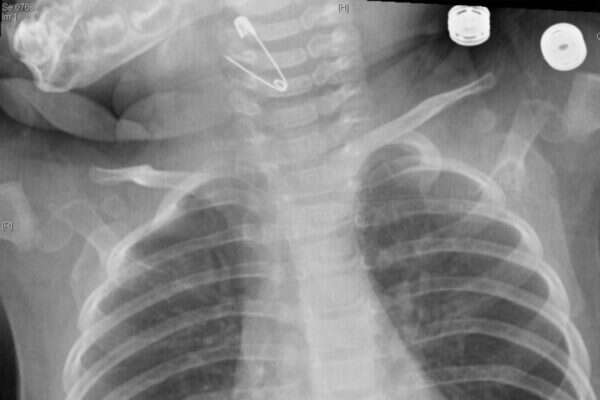

איתיאל חש עם בתו לבית החולים, שם טופלה במהירות על ידי ד"ר אבי בן יעקב, מנהל המרכז למחלות אף אוזן וגרון. "הצילום שנעשה לתינוקת הבהיר כי בגרונה נמצאת סיכת ביטחון פתוחה", ציין ד"ר בן יעקב. "נכנסנו לחדר ניתוח והצלחנו לשלוף את הסיכה מבלי לבצע חתך ומבלי שייגרם נזק כלשהו לדרכי האוויר של התינוקת. בשל היותה של הסיכה פתוחה היא יכלה בהחלט לפצוע אותה. התינוקת הושארה להשגחה אצלנו לכמה שעות ושוחררה לביתה".